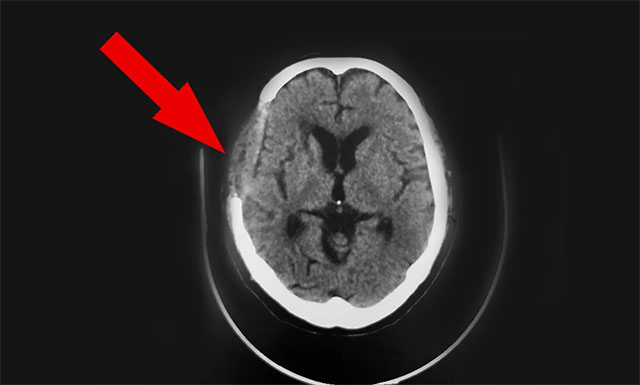

▲ 手术后

10月8日,双节的最后一天,患者神志清,精神佳,眼球各向活动好,伸舌居中,张口、鼓腮、吹起动作可,双肺呼吸音清,四肢肌张力正常,双侧巴氏征未引出。基于患者恢复可,予以办理出院。